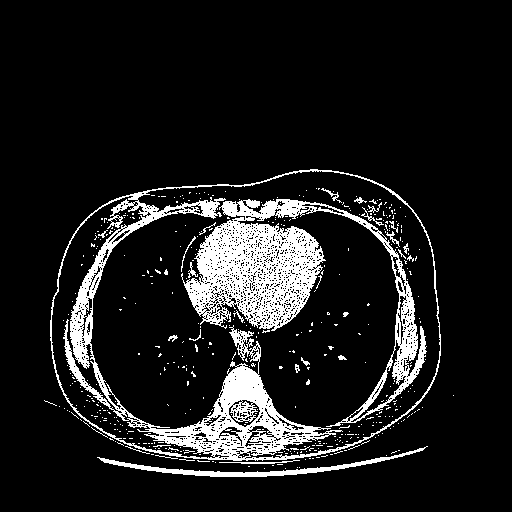

Reconstructed NATIVE CT scan (cycle consistency)

Full window (WL 1023.5, WW 4095 β†’ Low βˆ’1024, High +3071)

Actual HU range: [-1024.0, 3071.0]